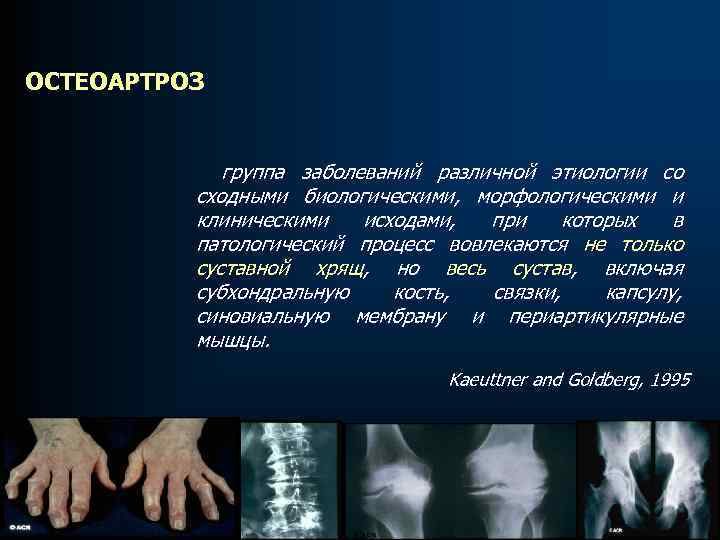

ОСТЕОАРТРОЗ группа заболеваний различной этиологии со сходными биологическими, морфологическими и клиническими исходами, при которых в патологический процесс вовлекаются не только суставной хрящ, но весь сустав, включая субхондральную кость, связки, капсулу, синовиальную мембрану и периартикулярные мышцы. Kaeuttner and Goldberg, 1995

ОСТЕОАРТРОЗ группа заболеваний различной этиологии со сходными биологическими, морфологическими и клиническими исходами, при которых в патологический процесс вовлекаются не только суставной хрящ, но весь сустав, включая субхондральную кость, связки, капсулу, синовиальную мембрану и периартикулярные мышцы. Kaeuttner and Goldberg, 1995